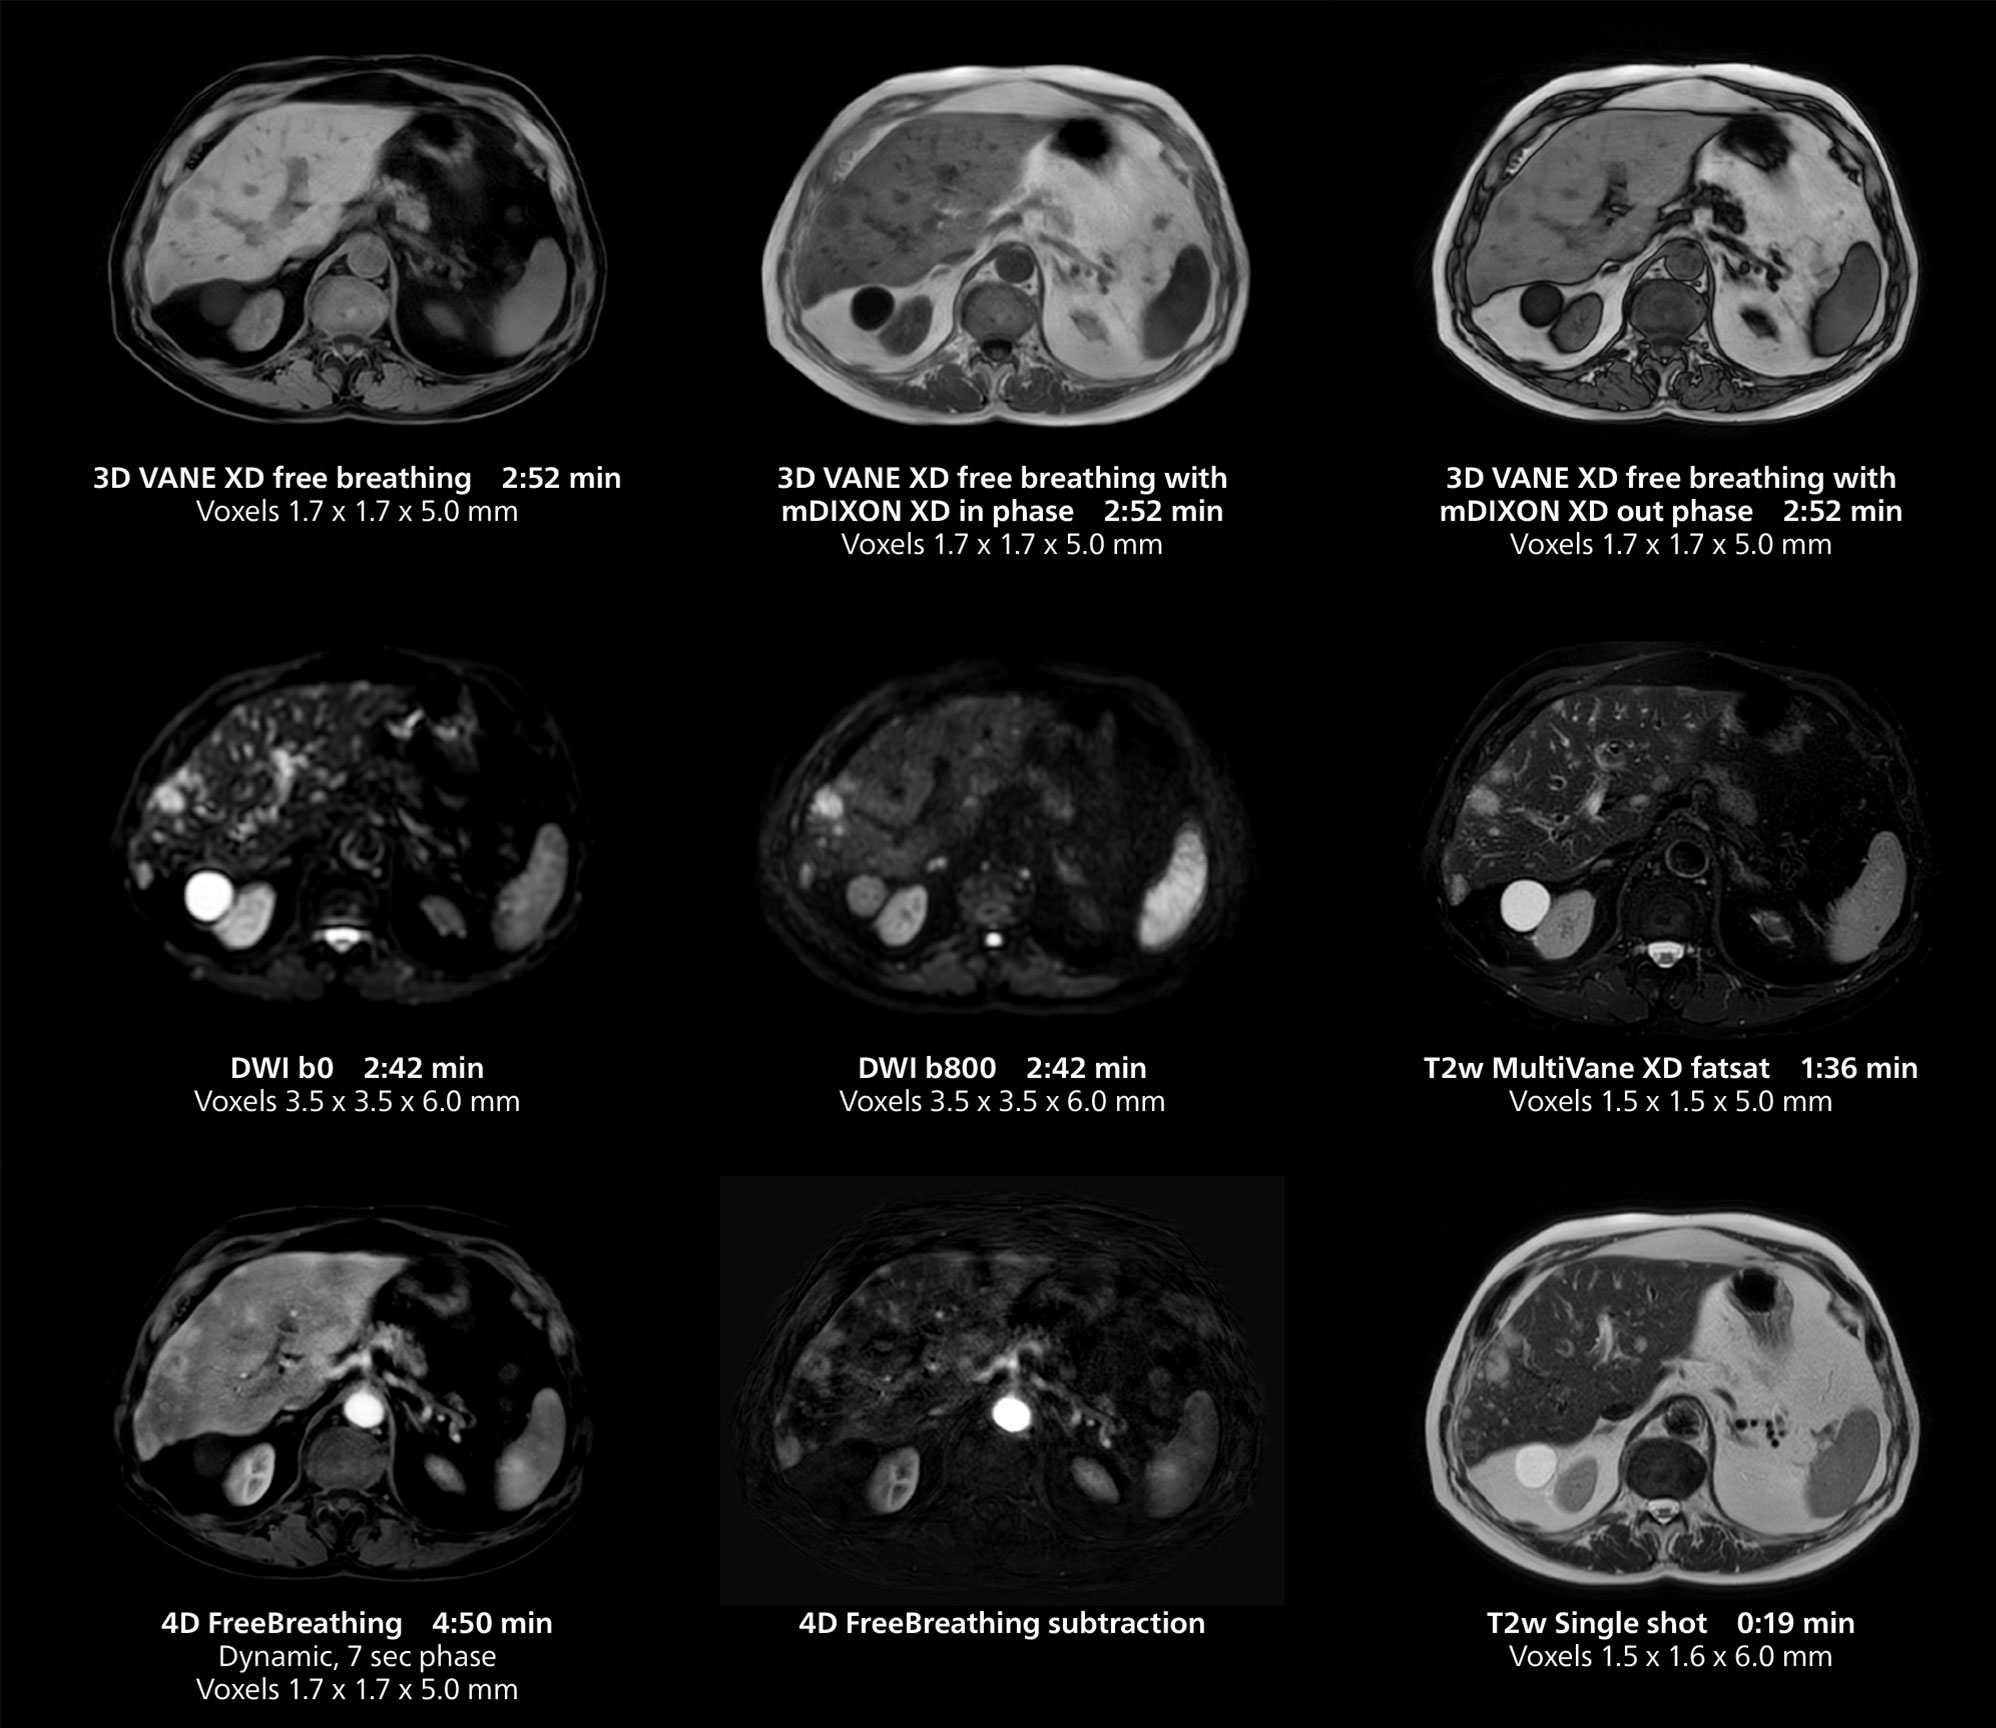

This case includes 3D free breathing and 4D dynamic free breathing MRI of a metastasized liver. A high quality fatsat sequence with good resolution is obtained in 1:36 minutes with T2-weighted MultiVane XD.

Dr. Gellée highlights the robust free-breathing scans as “the feature that makes the biggest difference in my daily work. The 3D free breathing sequences are very reproducible, and the axial acquisition is very good. For example, in endometriosis, which is one of my focus areas, it provides high contrast and good resolution so that I can see small details. We also use free breathing for liver and pancreas imaging. In multi-phase liver studies, 4D Free Breathing delivers 3-second temporal resolution, making a dynamic scan with more than one arterial phase possible.”

She also uses free breathing with 3D mDIXON to obtain in-phase, water and fat images in a single scan. “It is very reproducible before and after gadolinium, which makes it useful for liver imaging,” she adds.

This MRI case illustrates good resolution and imaging quality obtained within reasonable scan times using the MR 5300 1.5T system with the anterior torso cardiac coil that allows use of a large field of view (FOV).